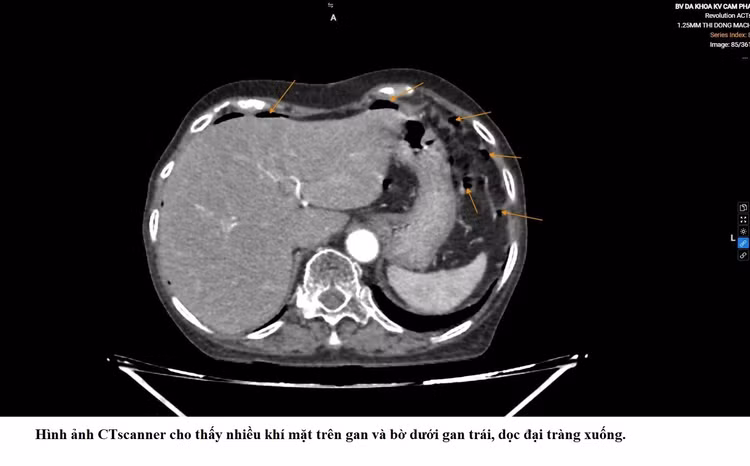

Qua thăm khám và các xét nghiệm cận lâm sàng, các bác sĩ xác định bệnh nhân bị viêm phúc mạc do thủng đại tràng trái và nhanh chóng chỉ định phẫu thuật nội soi cấp cứu.

Biểu hiện của thủng tạng rỗng trên phim chụp - Ảnh BVCC